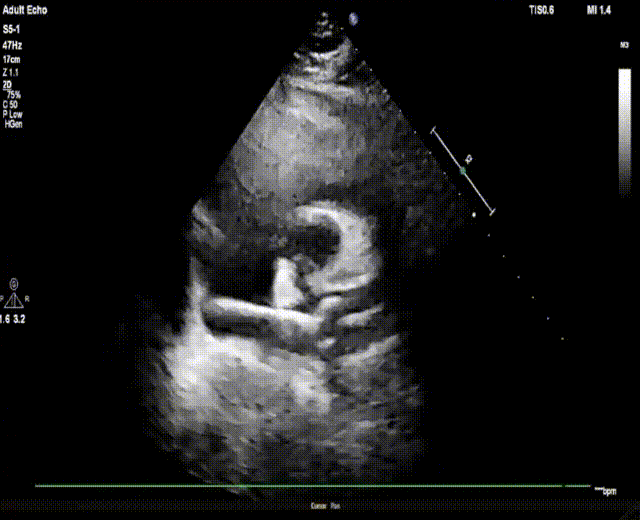

患者为41岁女性,存在金属过敏,既往偏头痛6年,头颅核磁提示存在多发脑缺血灶,右心声学造影提示心房水平大量右向左分流,符合PFO封堵指征。手术在单纯经胸超声指导下开展,术中操作较为顺畅,从建立工作路径到封堵器释放完成,整体手术仅耗时15分钟。术中经导管将28 mm×28 mm MemoSorb®可降解PFO封堵器精准送达卵圆孔未闭处后,在超声指导下严格遵循规范化5S操作步骤,先释放左盘面,牵拉成型线让左盘成型并贴壁稳定,继续回撤鞘管释放右盘面,超声下确认封堵器位置骑跨于缺损两侧、形态良好后,再次牵拉成型线。

上:左盘释放成型;下:右盘释放成型

锁定封堵器并使其完全成型后,释放封堵器,复查超声示封堵器紧贴房间隔,夹合牢靠,无残余分流!

术后超声